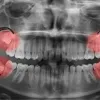

Tooth Removal

If a tooth must be removed due to damage, infection, or crowding, our team approaches the process with care and clear communication. Gentle techniques and detailed aftercare instructions help protect surrounding teeth and promote smooth healing.